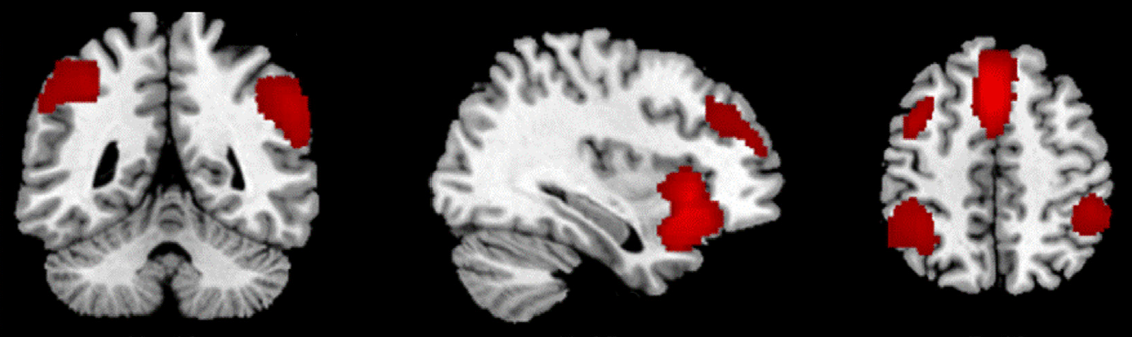

Is there a unique brain signature to deception? How neurologically do we manage the job of deceiving others? Can the findings of neuroscience provide insights for investment pros who look for the truth of the world each day? Each of these questions are answered by a...